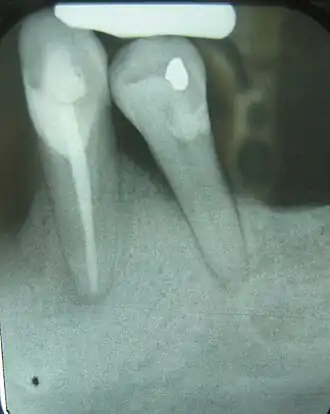

Esta radiografía de rayos X muestra un defecto horizontal .

La pérdida ósea generalizada se presenta con mayor frecuencia en forma de una pérdida ósea horizontal.[2]​ La pérdida ósea horizontal se manifiesta como un grado de reabsorción ósea algo uniforme, de modo que la altura del hueso en relación con los dientes ha disminuido de manera uniforme, como se indica en la radiografía a la derecha. Los defectos se producen adyacentes a un diente y, por lo general, en forma de una zona triangular de hueso faltante, conocida como triangulación.[3]